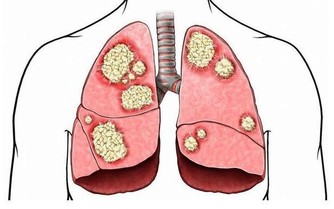

魔芋是世界上最優質的膳食纖維,具有很高的持水性,有較大的吸水性,持水大約相當於自身的1.5—2.5倍。從而可以增加人體排便體積和速度,減輕直腸壓力和泌尿系統壓力。可緩解膀胱結石,腎結石,使毒物迅速排出體外;同時,魔芋可以抵制腸道中產生的致癌物質的腐生菌生長,減少次生膽汁酸產生,減少致癌物質與結腸接觸的機會,產生丁酸,清除自由基—OH,從而防治胃癌及結腸癌等疾病。